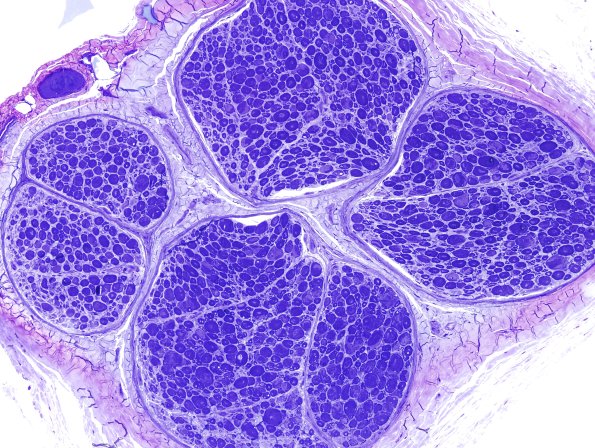

Washington University Experience | PERIPHERAL NEUROPATHY | 0 PNS ARTIFACTS | 12C1 Artifact, crush compare with adjacent block same nerve Plastic 20X 2.jpg

12C1.2 Two adjacent blocks with the first cut before complete fixation and the second after fixation. (Toluidine blue stained one micron thick plastic embedded sections)